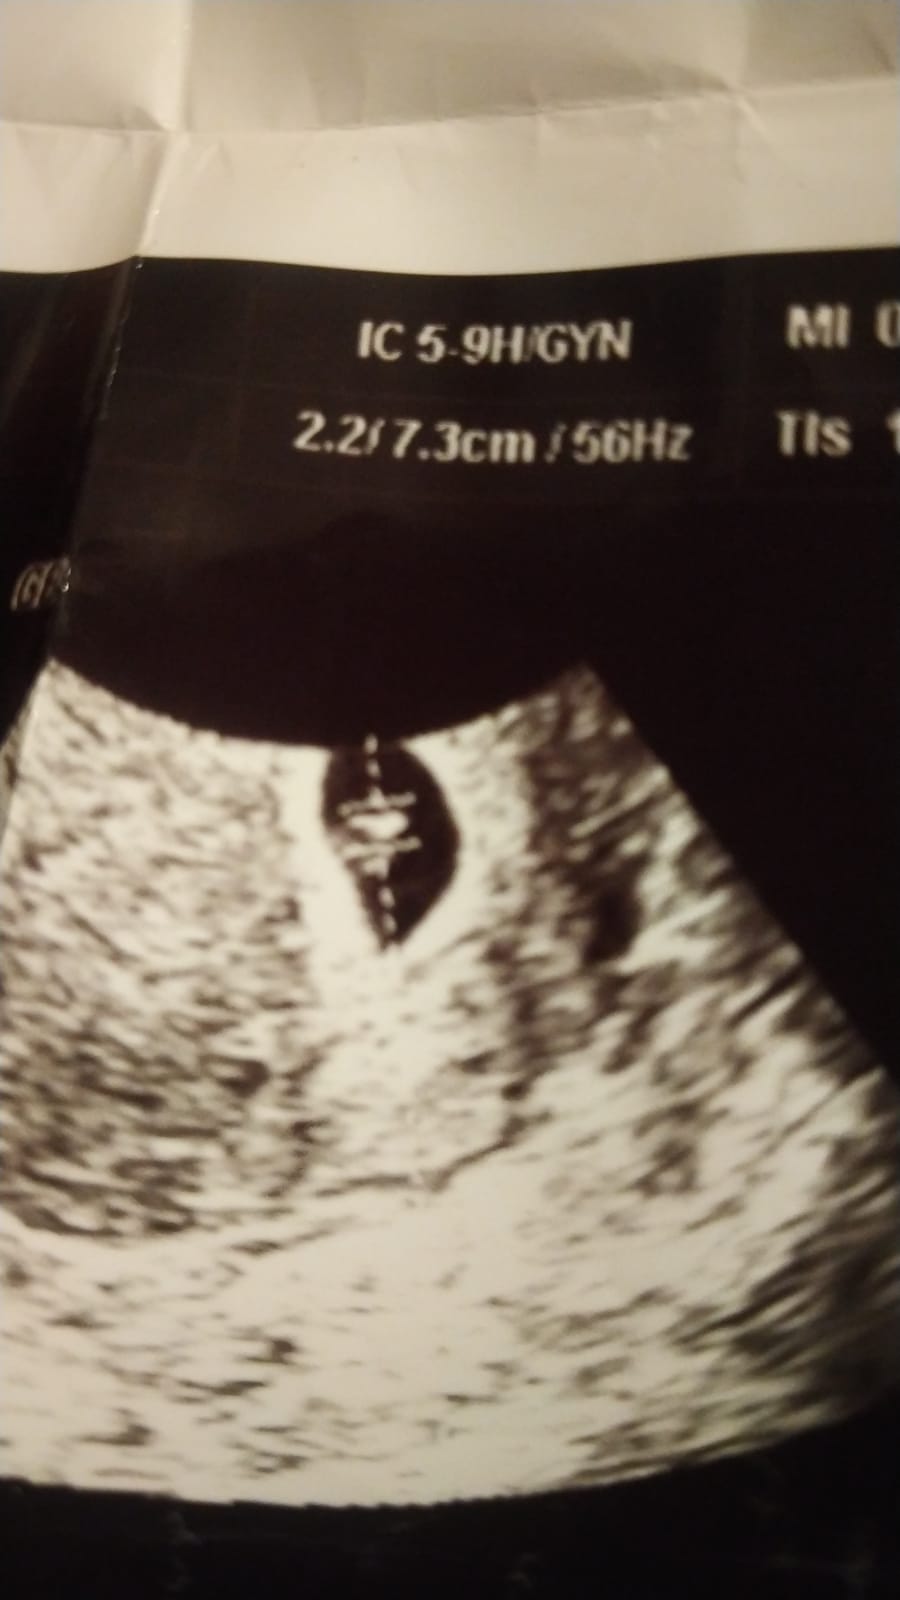

Selamlar hayatım. Resim inanılmaz derecede bulanık daha net resim var ise atın bakalım. Bu tür durumlarda tahmin inanılmaz şekilde zor oluylor. Yani söylemek için de söylemek bizlere uymuyor istiyoruz ki gördüğümüzü söyleyelim ama göremiyoruz 🙂

Bi tanem tekrar selamlar yok hayatım çok küçük vallahi göremiyorum hakkını helal et lütfen. Resimler olmuş sıkıntı yok ama sıkıntı görünmeyecek kadar yeni ve küçük olması netlik yok hayatım kusura bakma lütfen.

Yok estagfurullah ne demek allah razı olsun siz helal edin baktınız yinede minnettarım cok teşekkür ederim 6 haftalık burda oyuzden sanırım 2 hafta sonra kontrolüm var 8 haftalık olanı attıgımda onada bakıp yorumlarmısınız peki lütfenn